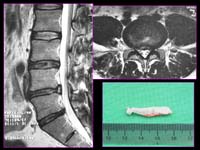

<Ç㸮µð½ºÅ©>

<¼ö¼úÀü>

<¼ö¼úÈÄ>

Á¦

4.5¹ø ¿äÃߺΠÃß°£ÆÇ Å»ÃâÁõÀ¸·Î ¼ö¼úÇÑ

ȯÀÚÀÇ ¿äÃß MRI¼Ò°ßÀ¸·Î ¼ö¼úÈÄ Å»Ãâ

µð½ºÅ©ÀÇ Á¦°ÅµÈ ¸ð½À°ú ÀûÃâµÈ µð½ºÅ©¸¦

º¼ ¼ö ÀÖ´Ù.

<ô¼öÁ¾¾ç>

<°æÃߺÎ

»óÀǼ¼Æ÷Á¾> <ÈäÃߺÎ

¼ö¸·Á¾>

|